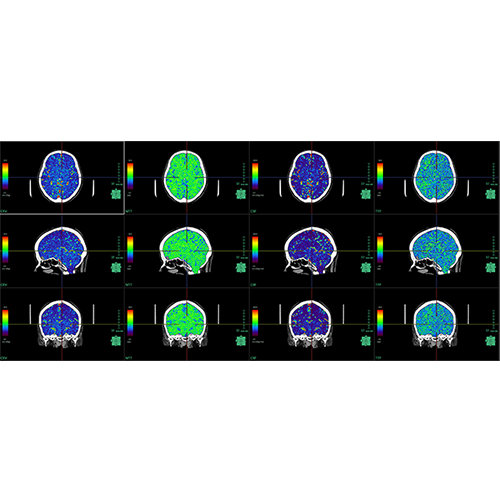

Traditional multi-planar slicing

Multi-planar slicing.

Oblique slicing.